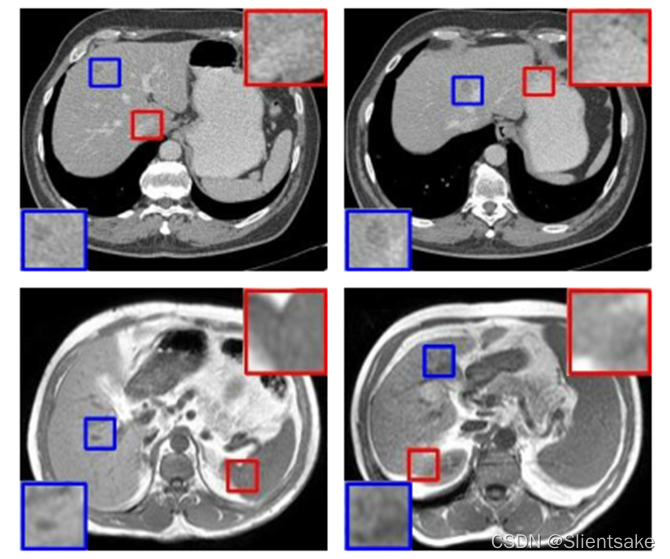

其次,更典型的是,目标对象的类内异质性和边界模糊仍然是医学图像分割中的巨大挑战,如图1所示。

图1所示。通过两个腹部CT图像(第一排)和两个腹部MR图像(第二排)的例子显示了医学成像中的类内异质性和边界模糊。蓝色矩形和红色矩形分别表示外观不均匀和边界模糊。

如图1所示,再次回顾了上述医学成像中的挑战:1)类内异质性,即不同图像中的目标对象共享相同的语义标签,但外观不同。例如,在肝脏分割中,个体解剖差异和成像设备的差异都可能导致类内异质性。特别是在训练数据有限的情况下,网络对类内不一致很敏感,容易过拟合。2)边界模糊,靶器官和邻近组织之间的低对比度,这通常发生在成像时。由于传统的fcn在这个场景中是过度参数化的,它往往在训练数据集上表现良好,而在测试数据集上表现较差。因此,如何在准确建模目标对象的流形和鲁棒地表示个体差异之间取得平衡是代理监管的关键。